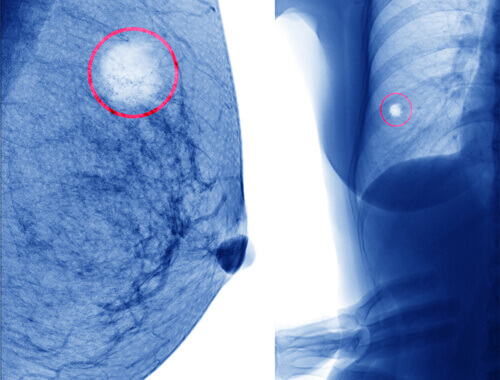

En brystcyste er en samling av væske på innsiden av brystet. Det er en liten sekk, vanligvis på størrelse med en kikert eller mindre, som vanligvis inneholder væske.

Mens flertallet av brystcyster er fylt med væske, er det også godartede cyster som er mer solide.

Det er en annen type cyste som kalles fibroadenom. Disse har en tendens til å være symptomfrie og smertefrie. Vanligvis kan du oppdage dem under en brystundersøkelse ved å kjenne en liten, hard, bevegelig klump i brystet.

Det vil generelt føles enten glatt eller litt grovt når det er forårsaket av et fibroadenom, med fliker når du berører det. Den vil bevege seg fritt rundt i brystet når du berører den.

Heldigvis er de også godartede. Fibroadenomer oppstår når det er overdreven vekst av brystvev. Også, selv om de kan forveksles med brystcystene som vi beskrev ovenfor, er de forskjellige.